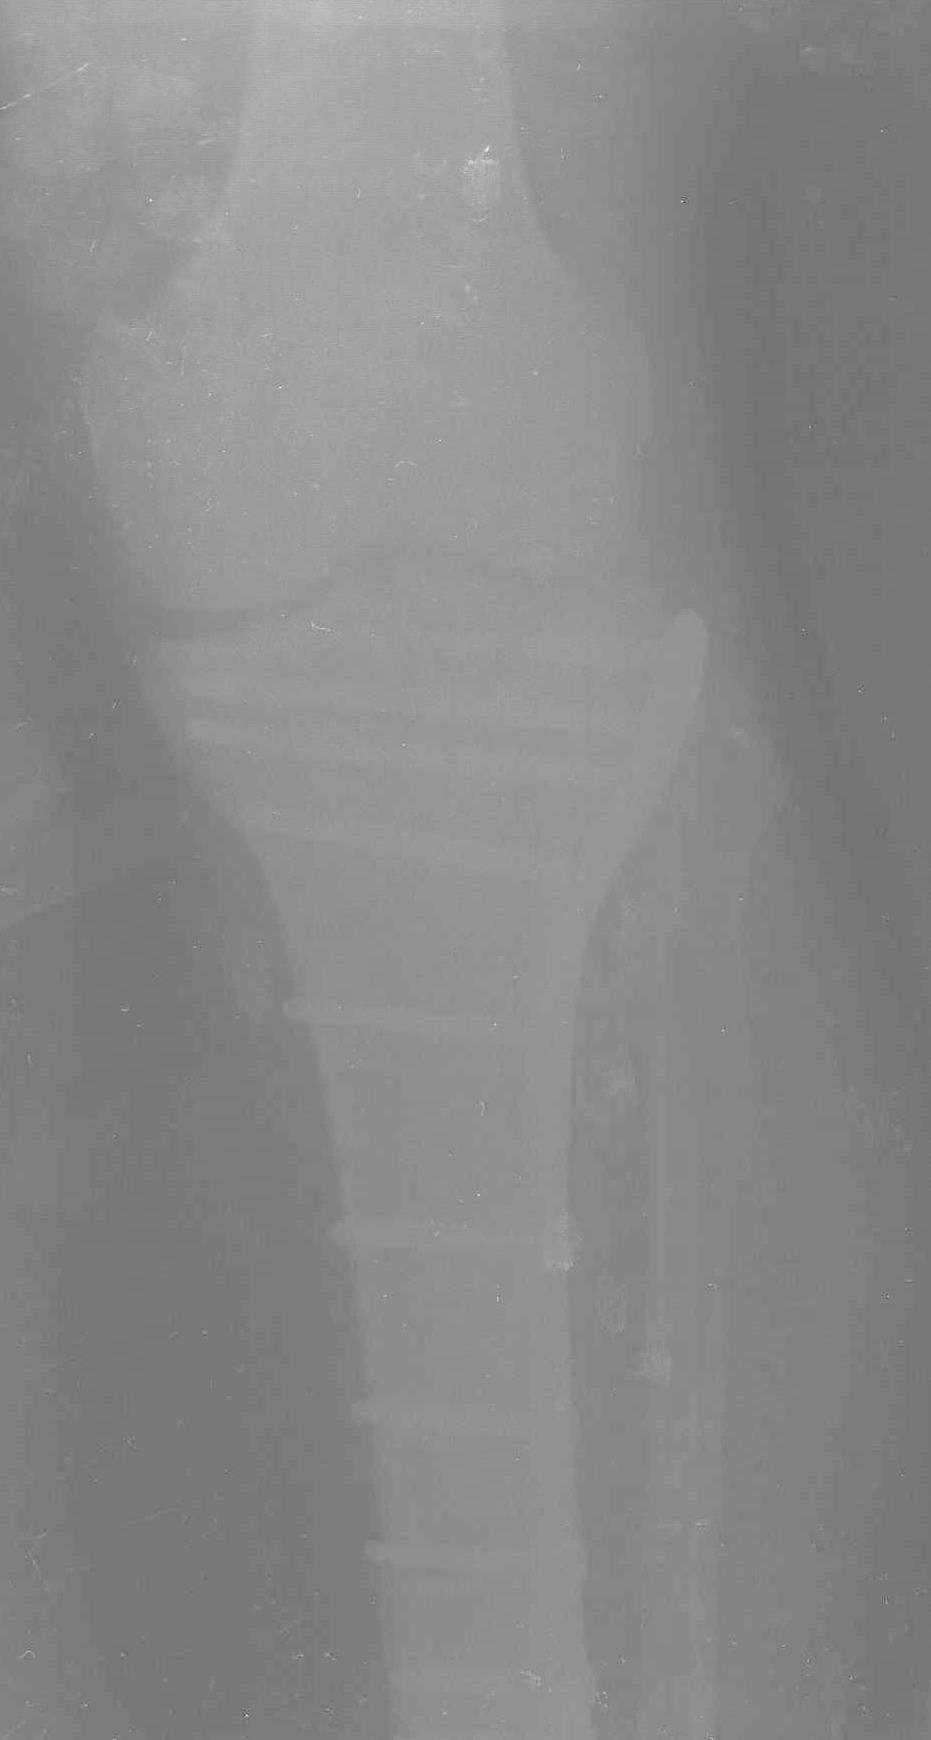

Надеюсь, представленные снимки разных случаев помогут разобраться в тактике, и критика примется без личной обиды.